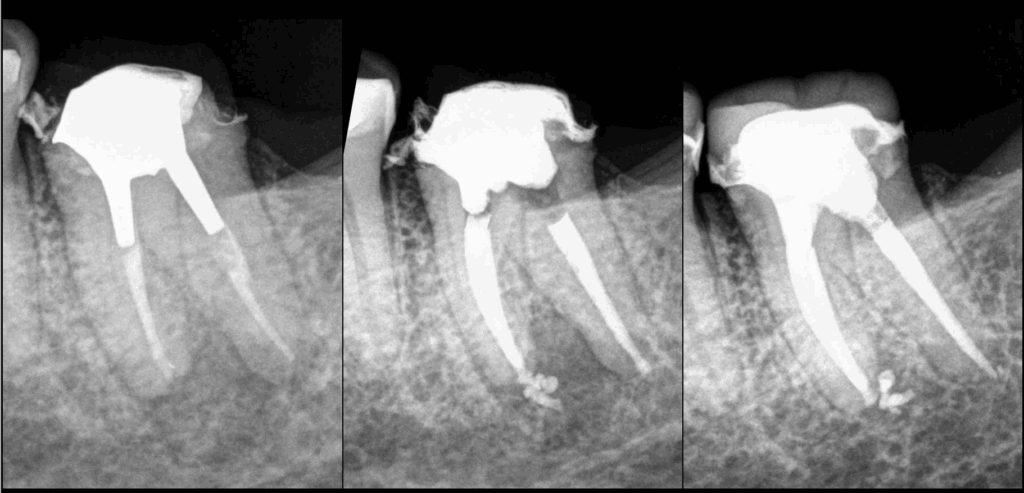

🔍 Couronne déposée par notre correspondant

➡️ 𝐄́𝐯𝐚𝐥𝐮𝐚𝐭𝐢𝐨𝐧 𝐞𝐧𝐭𝐫𝐞 𝐬𝐞𝐬 𝐦𝐚𝐢𝐧𝐬 𝐝𝐞 𝐥𝐚 𝐩𝐨𝐬𝐬𝐢𝐛𝐢𝐥𝐢𝐭𝐞́ 𝐝𝐞 𝐫𝐞𝐬𝐭𝐚𝐮𝐫𝐞𝐫 𝐥𝐚 𝐝𝐞𝐧𝐭 𝐝𝐞 𝐟𝐚𝐜̧𝐨𝐧 𝐟𝐢𝐚𝐛𝐥𝐞 𝐞𝐭 𝐩𝐞́𝐫𝐞𝐧𝐧𝐞.

🔄 𝐑𝐞𝐭𝐫𝐚𝐢𝐭𝐞𝐦𝐞𝐧𝐭 𝐜𝐚𝐧𝐚𝐥𝐚𝐢𝐫𝐞 𝐝𝐞 𝐧𝐨𝐭𝐫𝐞 𝐜𝐨̂𝐭𝐞́.